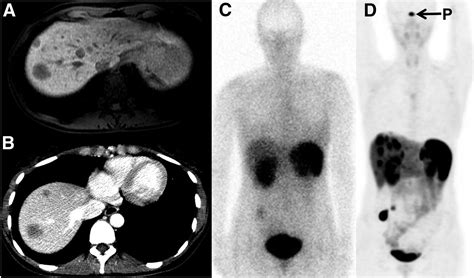

A Dotatate PET scan—often formally referred to as a Gallium-68 (Ga-68) DOTATATE PET/CT scan—is a sophisticated type of molecular imaging. Unlike conventional scans like CT or MRI, which primarily look at the size and shape of body structures, a PET scan focuses on how cells function at a molecular level.

The "Dotatate" component is a radioactive pharmaceutical agent. It acts as a targeted seeking device that binds to somatostatin receptors. These receptors are often found in high concentrations on the surface of neuroendocrine tumor cells. Because these tumors "light up" when the tracer binds to them, the PET scan creates a vivid map of where these tumors are located throughout the body, even those that are too small to be detected by standard imaging.